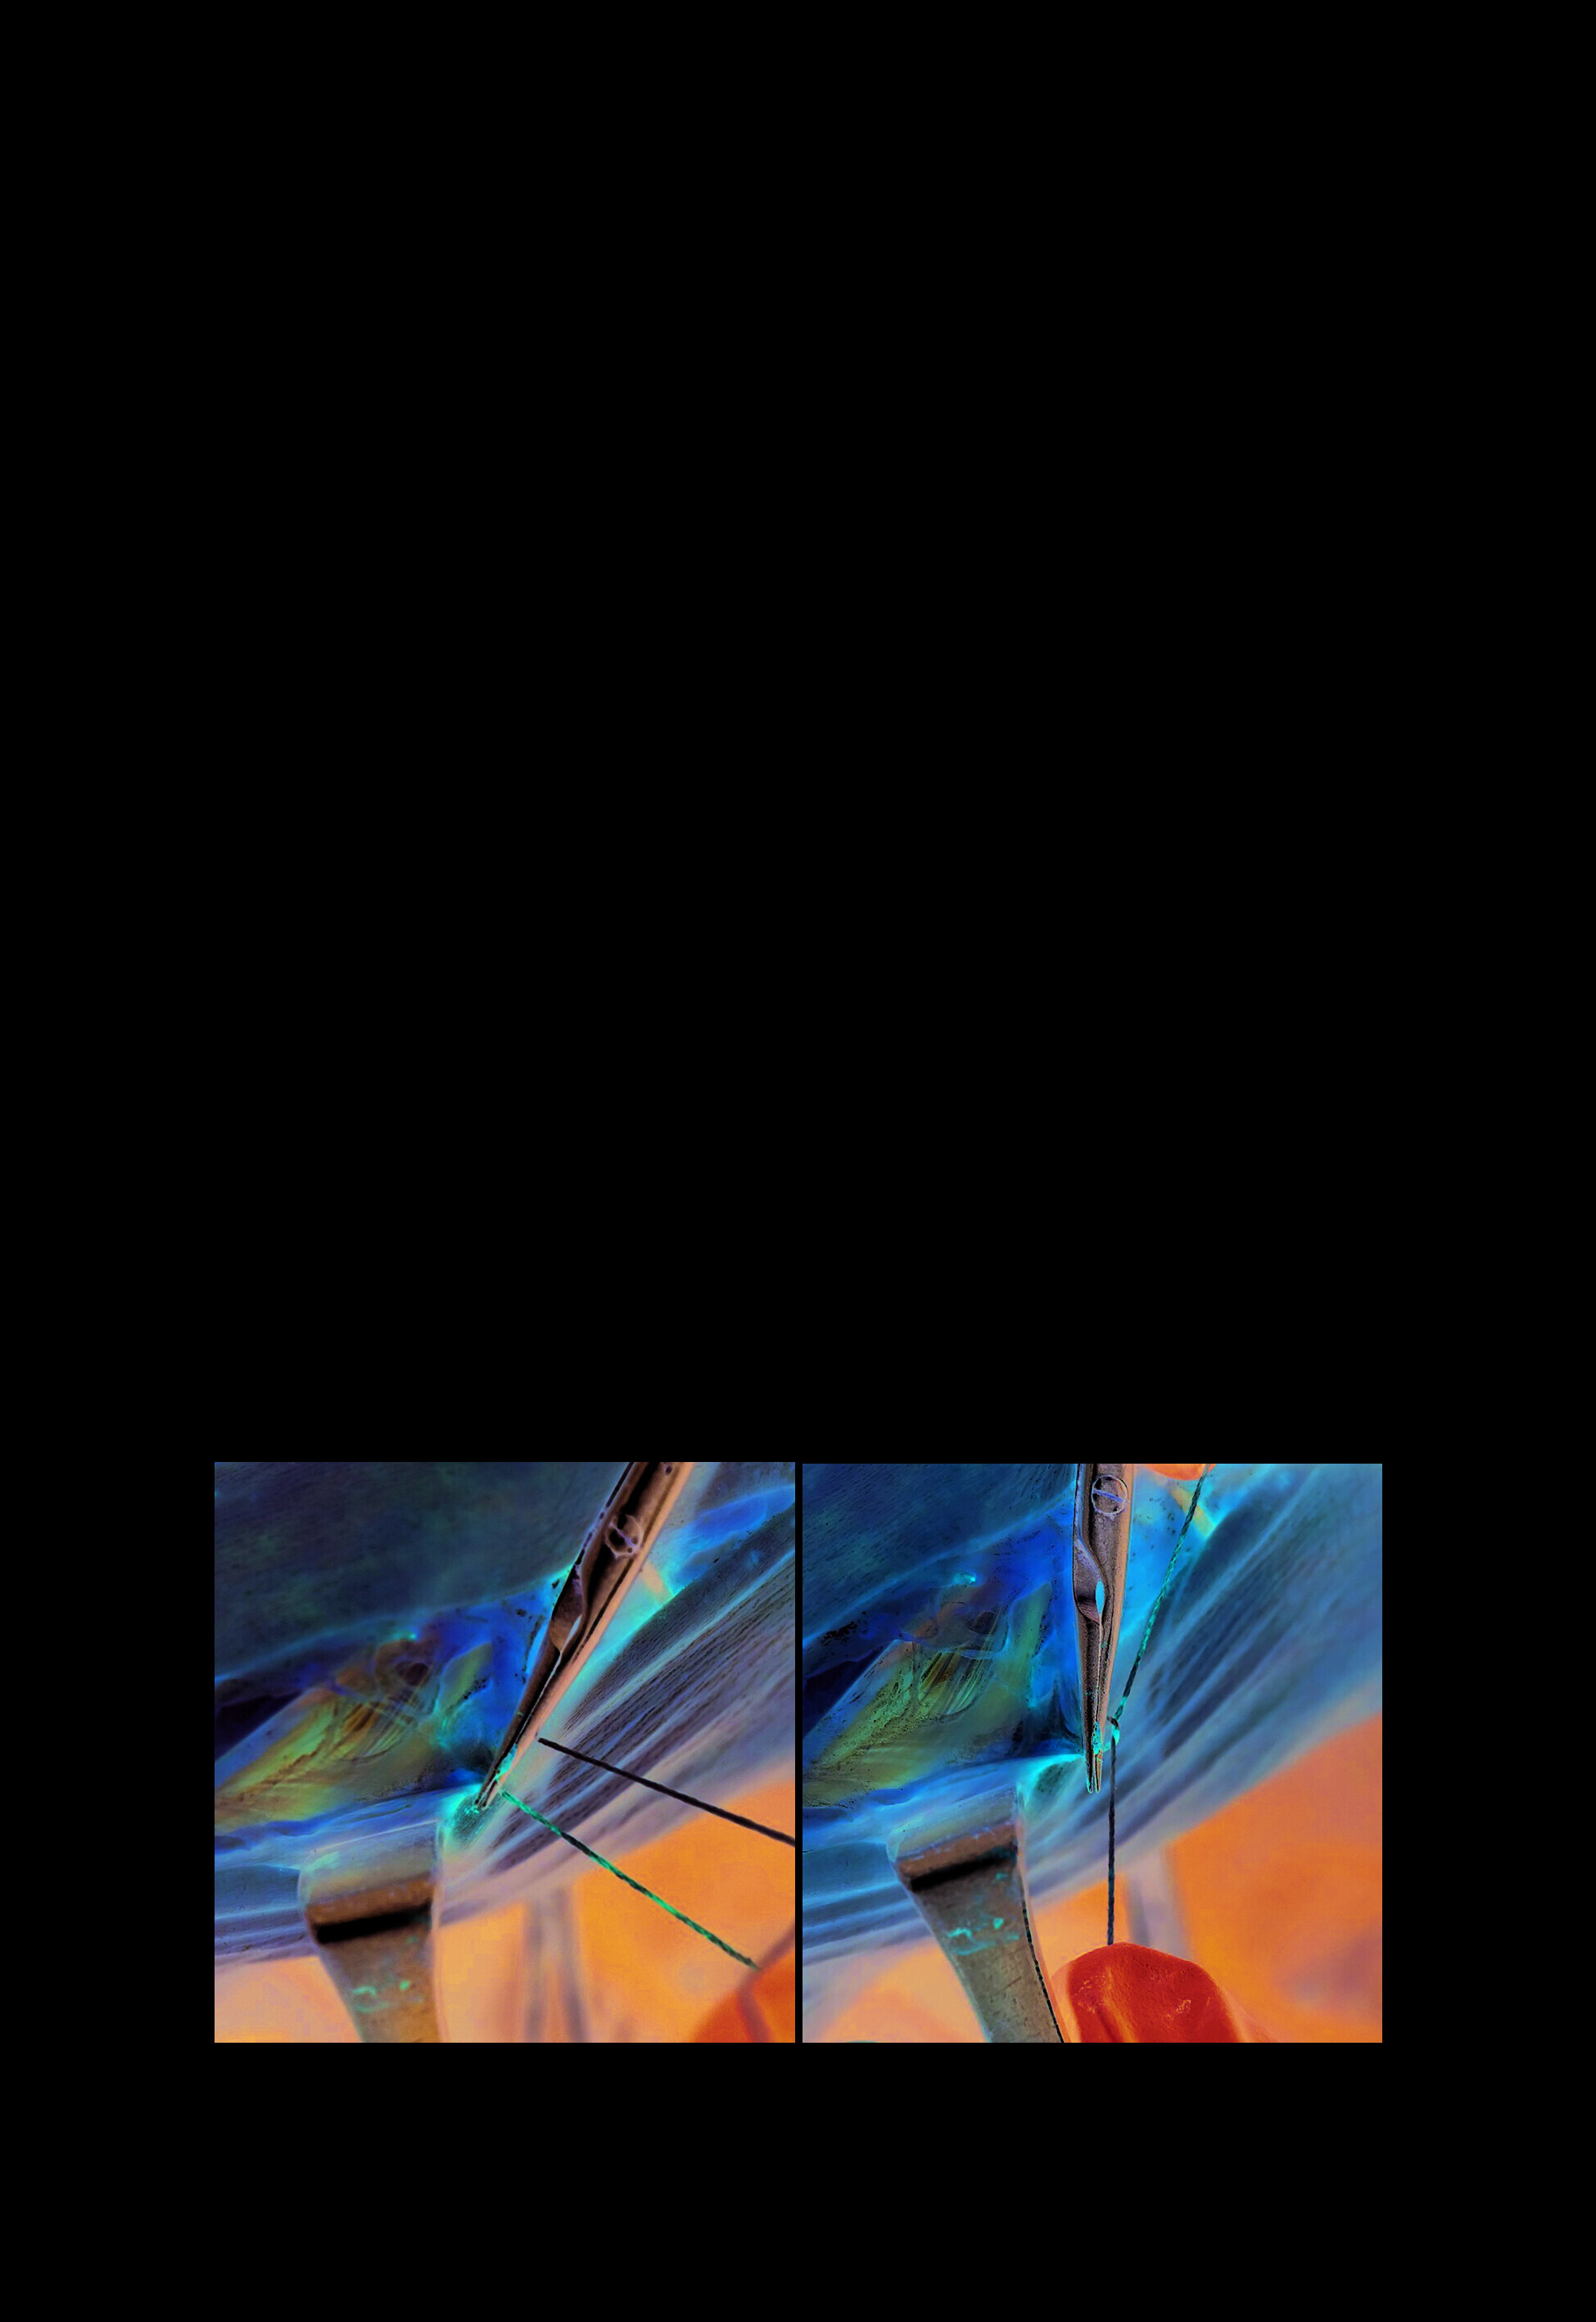

Руководство к практическим занятиям является результатом работы сотрудников кафедры оперативной хирургии и топографической анатомии Сеченовского Университета и позволяет совершенствовать процесс обучения студентов основным элементам оперативной техники.

Руководство к практическим занятиям является результатом работы сотрудников кафедры оперативной хирургии и топографической анатомии Сеченовского Университета и позволяет совершенствовать процесс обучения студентов основным элементам оперативной техники.